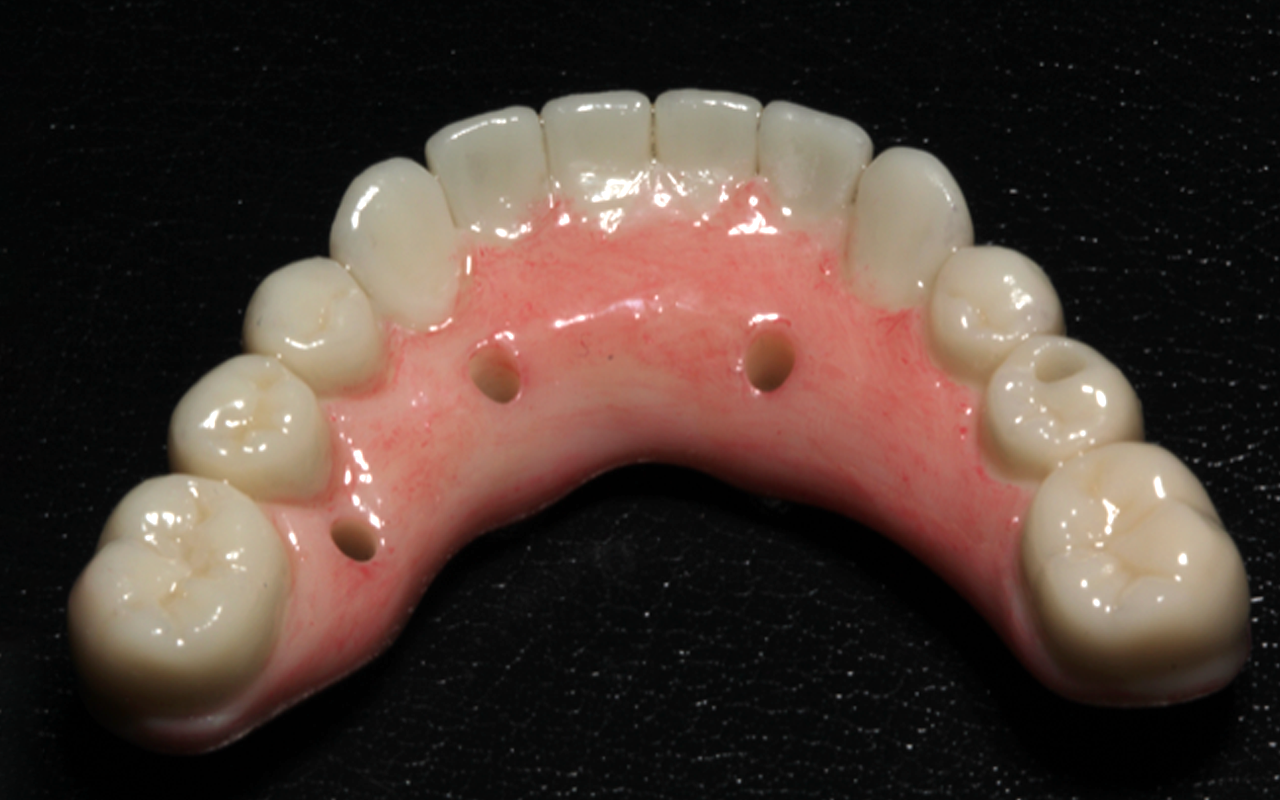

2) Full-arch straight and tilted implant placement and restoration in special plastic models

Full arch patient surgery with 3D surgical and stackable guides, implant scanning protocols with 3Shape and photogrammetry with PIC scanner and the delivery of a 3D printed full arch provisionals.